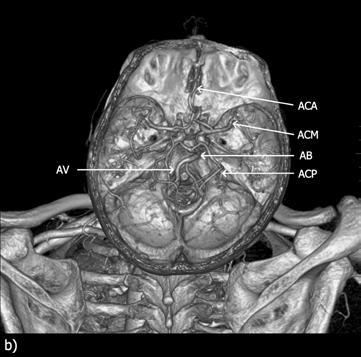

Obr. 2.25 Cévní zásobení mozku – CT angiografie (snímek z vyšetření Jakub Čivrný)

CT angiografie, 3D rekonstrukce v provedení tzv. maximum intensity projection (MIP), frontální pohled.

AB – arteria basilaris, AV – arteria vertebralis, ACI – arteria carotis interna, ACC – arteria carotis communis, Ao – aorta

Obr. 2.26 A + B Willisův okruh – CT a MR angiografie (snímek z vyšetření Jakub Čivrný)

Srovnání MR a CT angiografie. MR angiografie mozku, metoda time-of-flight (TOF), rekonstrukce maximum intensity projection (MIP) (a); CT angiografie mozku, 3D rekonstrukce (b).

ACA – arteria cerebri anterior, ACM – arteria cerebri media, ACI – arteria carotis interna, ACP – arteria cerebri posterior, AB – arteria basilaris, AV – arteria vertebralis